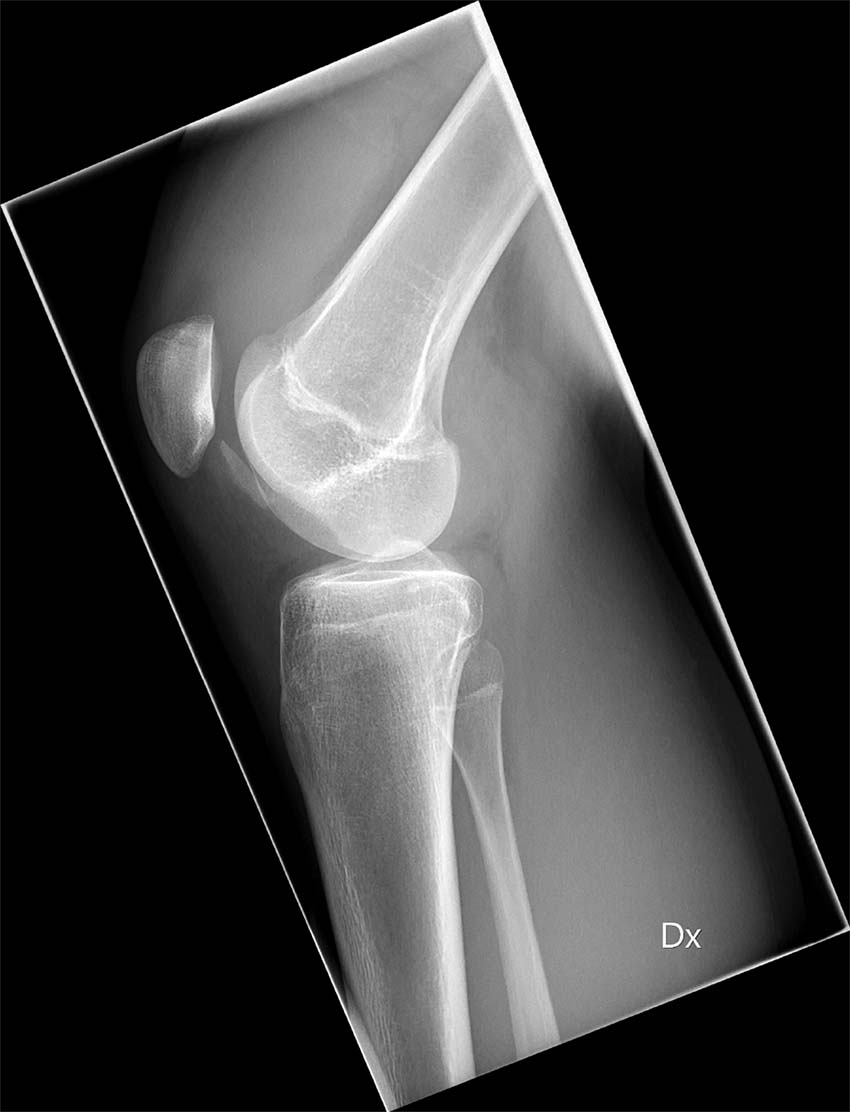

Slätröntgen

Slätröntgen av knät bör omfatta tre projektioner: anteroposterior, lateral med knät i 30 graders flexion samt femoropatellär vy (Merchants vy) [11]. Subluxation, patellar tilt och trochleadysplasi värderas med Merchants vy, medan patella alta bedöms lättast med den laterala vyn.

Bilddiagnostisk undersökning i det akuta skedet är nödvändig för att kunna bedömma helhetsbilden och utesluta både fraktur samt fria osteokondrala fragment. Slätröntgen bör tas i tre olika plan: anterioposteriort, lateralt samt femoropatellärt. Detta för att kunna utvärdera den patellofemorala leden samt, om möjligt, upptäcka skelettskador/andra abnormaliteter.

I vissa fall kan osteo­kondrala fragment identifieras med slätröntgen. Notera ett halvmåneformat fragment strax inferiort om patella.